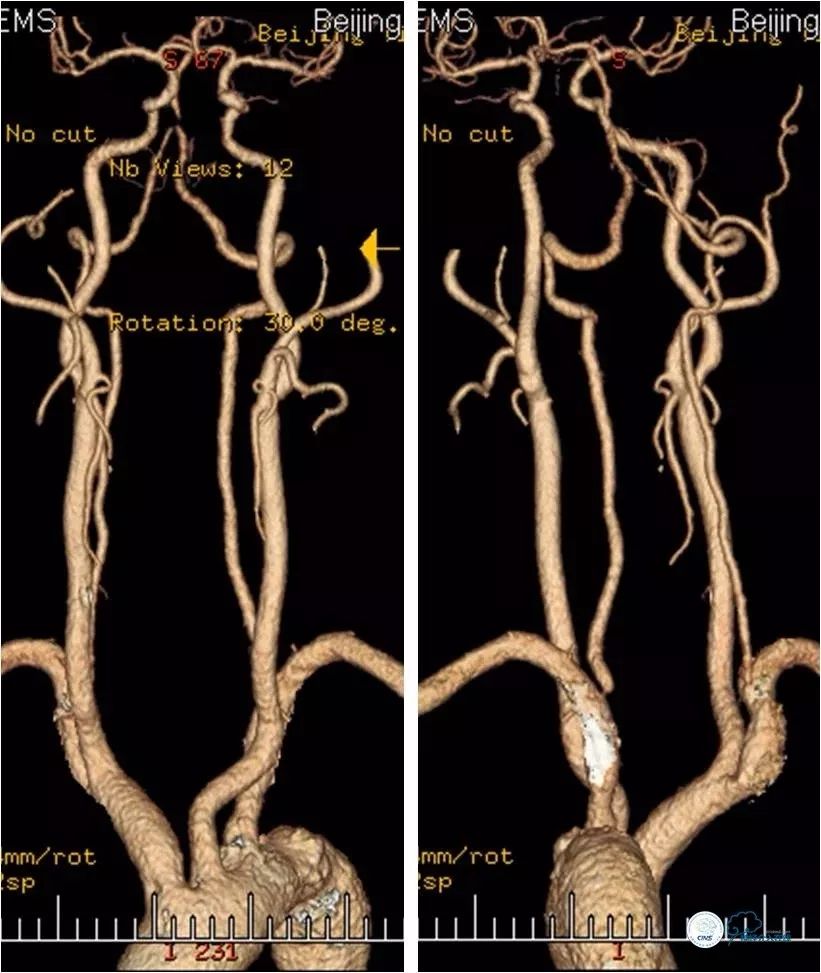

弓上CTA(2018-7-2):左椎动脉开口处重度狭窄,双侧椎动脉V4段-基底动脉重度狭窄(图3)。

图3